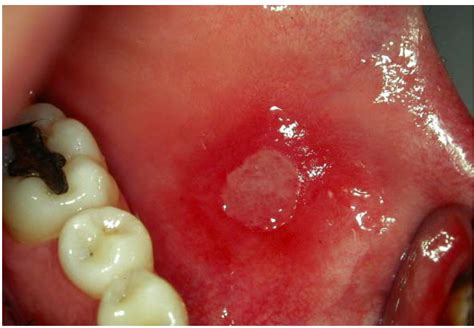

What is mucositis & why is it painful?

Mucositis describes inflammation and ulceration of the digestive tract lining. It can cause painful sores in the mouth or gastrointestinal symptoms. It often results from cancer treatments. When the thin mucous membrane that lines the digestive tract becomes inflamed, it can be painful.